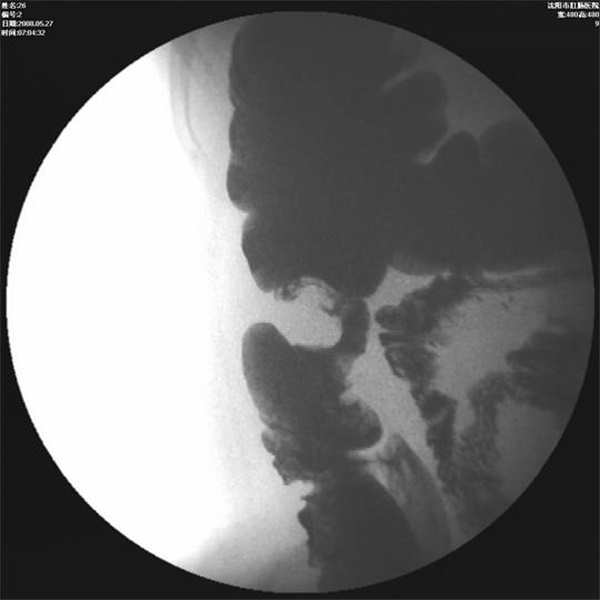

1、排便造影

排便造影就是将钡剂模拟粪便灌入直肠内,患者坐在易透X光的排便器上,在患者排便的过程中,多次摄片或录像,以观察肛管、直肠的影像学改变,动态观察钡剂排出(模拟排便)过程中肛门和直肠的功能变化。排便造影能为会阴下降、直肠前突、直肠前壁粘膜脱垂、内套叠、盆底疝、内脏下垂、耻骨直肠肌肥厚等疾病的诊断及鉴别诊断提供可靠的依据.

直肠前突合并会阴下降

直肠前突合并直肠前壁粘膜脱垂